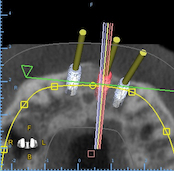

To some, "Guided Surgery" is a mixture of buzzwords, expensive tools, and tedious process flows.  In this course Guided Surgery is shown as it is meant to be: tools that work for you, software that assists the implant planning process and surgical guides that improve the safety and accuracy of the implant placement.  This course introduces the viewer to the simplicity of guided surgery.

This course shows how to streamline the entire guided surgical process by giving full control to the user. The course demonstrates how software can be a platform allowing users to control the entire planning and guide fabrication process or to collaborate and benefit from the help of labs and / or other dental professionals.